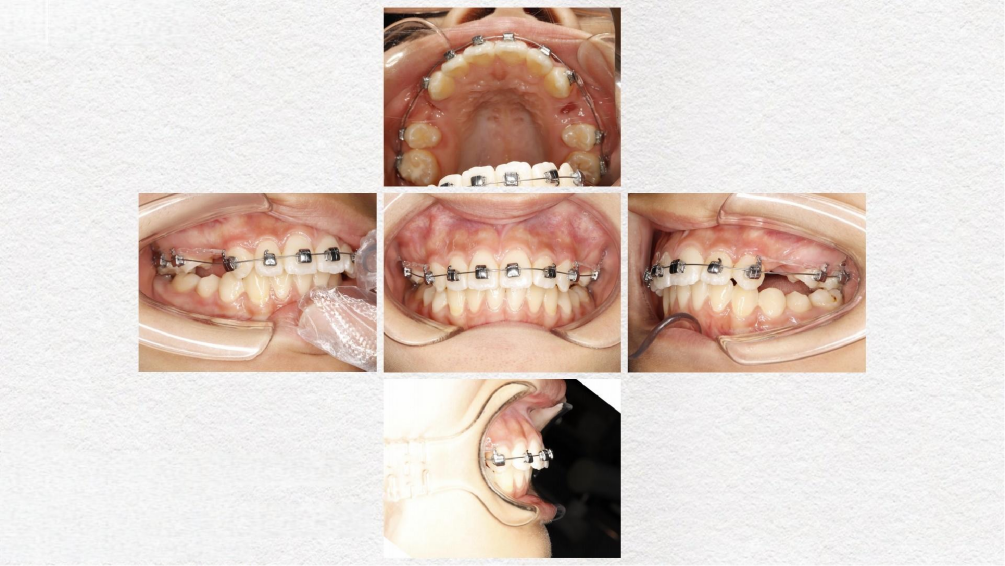

临床案例